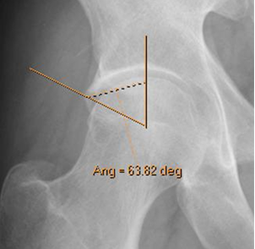

Fig 97. Pinzamiento tipo pincer. Signo del ángulo de borde lateral.

Rx AP. Angulo de cubrimiento lateral, mayor de 40º.